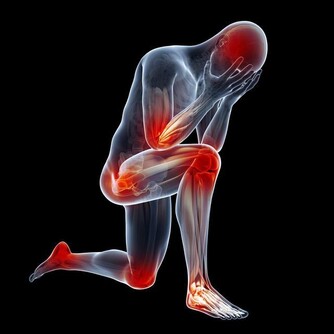

頸椎、腰椎扭傷是一種常見病、多發病。當前對頸椎、腰椎發生扭傷,一般都按照常規的方法治療,頸椎有病治療頸椎,腰椎有病治療腰椎,但對頸椎和腰椎鄰近椎體的治療,往往被忽略了,而這恰恰又是治療頸椎、腰椎扭傷,提高療效的關鍵所在,做為醫者不可不知也。

因為有了這一次治療頸椎和胸椎的經驗以後,發現很多患有頸椎病、腰椎病的人,在頸椎以下、腰椎以上相連接的椎體上,均存在著錯位,因此,得出一條重要結論:頸椎有病連著肺,腰椎有病連著胃。

這句話講的是什麼意思呢?頸七椎向下相連的是胸椎的一椎、二椎,這兩個椎體與肺相通,是通往肺的通路,當頸椎扭傷一定牽連到胸椎的一、二椎;腰椎向上相連的是胸十椎、十一椎、十二椎,十一椎、十二椎與脾、胃相通,是通往脾胃的通路,當腰椎扭傷一定牽連到胸十、十一椎。

如此看來,我們在對頸椎錯位治療的同時,要顧及到胸椎的一、二椎的檢查和治療,腰椎錯位的治療,要顧及到胸椎的十、十一、十二椎的檢查和治療,與頸、腰椎相連接錯位椎體的治療,即是對本病的恢復起到治療作用,同時,也有利於頸、腰椎的治療。這些與之相連的椎體錯位,患者也一定會出現相聯繫臟腑的病症反應。以上對頸、腰椎檢查方法,對病症的判斷,以及治療的範圍,做為醫者不可不知也。

頸椎下端和腰椎上端的這些部位,往往是在臨床中被遺忘的角落,所以,既影響頸、腰椎的治療,也影響與之相連病症的治療效果。醫者在治療頸椎腰椎的同時,一定要檢查鄰近胸椎椎體的排列狀態,頸椎的治療要注意到肺(胸一、二椎),腰椎的治療要注意到胃(胸十、十一椎),這是治療頸椎腰椎病症的關鍵。